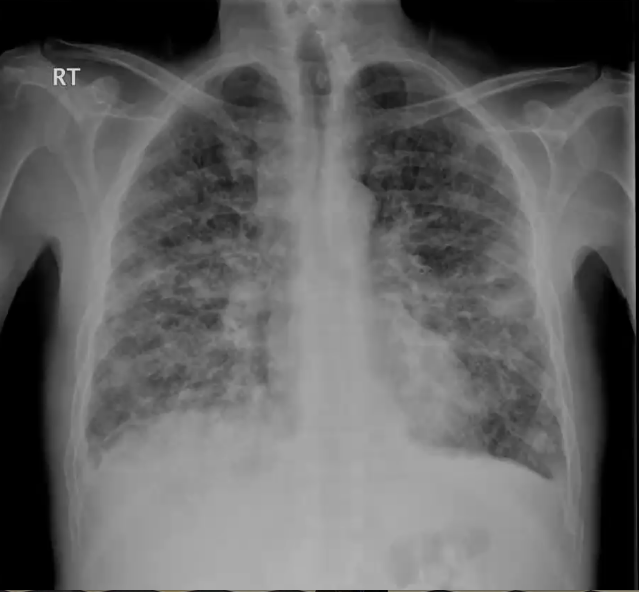

What’s your diagnosis?

ARDS